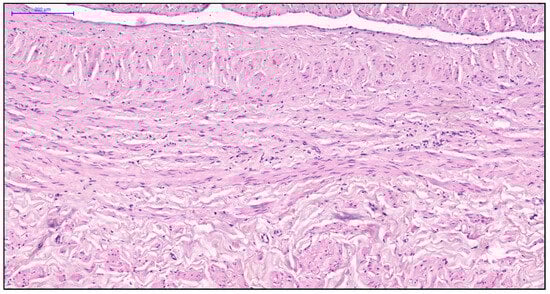

More pronounced structural alterations appear in the great saphenous vein of middle-aged and elderly individuals under normal conditions. Age-related changes manifest as uneven wall thickness and structural heterogeneity. Areas with thinner walls show reduced proportions of longitudinal and circular smooth muscle layers, while thicker regions contain these layers at maximal density (Figure 2 and Figure 3). The circular smooth muscle bundles become increasingly separated by connective tissue, creating a disorganized appearance.

Figure 3. Fragment of the great saphenous vein in individuals of the second age group. Hematoxylin and eosin staining. Magnification × 200. Clearly defined layer of longitudinally oriented smooth muscle cells of the middle layer.